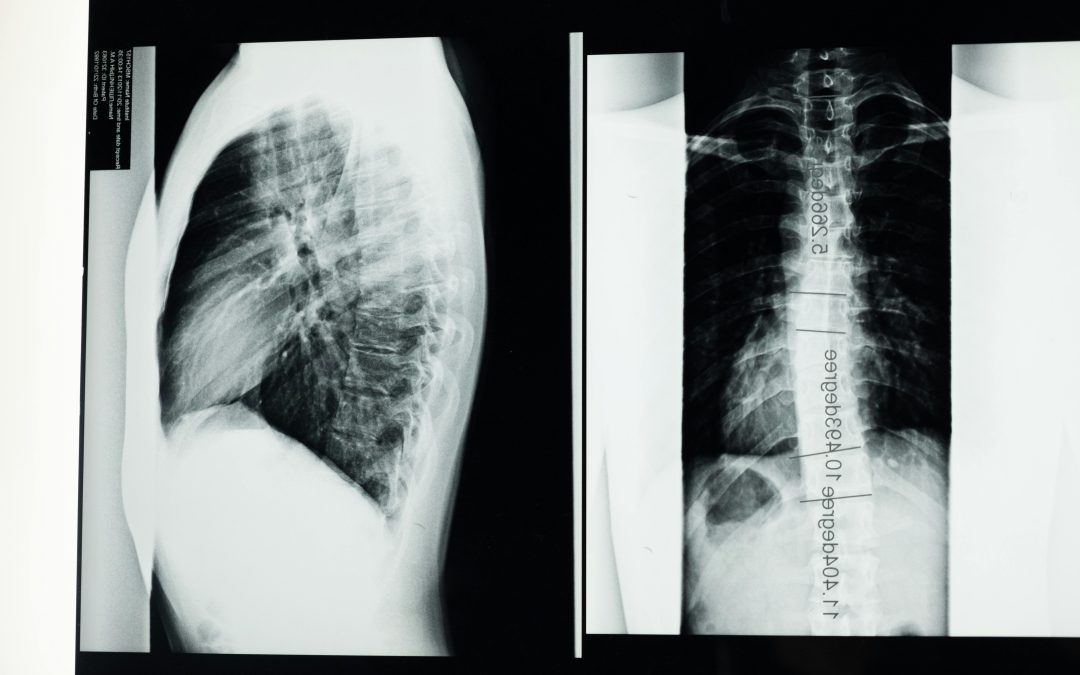

If you’re dealing with back pain, numbness, or tingling, you might be wondering if an X-ray can show a herniated disc. After all, X-rays are commonly used to diagnose bone and joint issues. The short answer? No, a standard X-ray cannot directly show a...